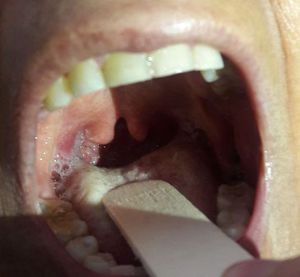

well done .Just bifid uvula not tonsillitis. It doesn't have even erythema.

About the tongue is this oral candidiasis or just reflection of the the light cuz the photo is not clear

İt can be fungal. Itrakonazol is a good choice. However there is a possibility of HIV(+)

No! some help. Bifid uvula is seen in Digorge syndrome. You know the others, try it.😊